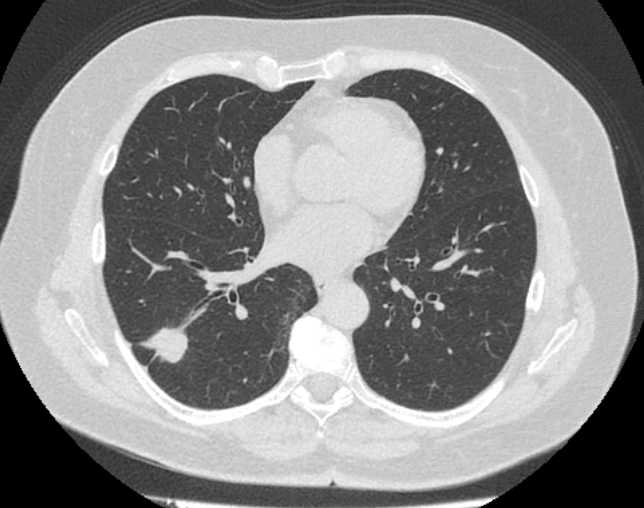

Во время исследования рентгеновская трубка томографа вращается вокруг исследуемой области и производит множество послойных снимков с шагом 0,5-1 мм. Полученные снимки поперечного сечения с помощью компьютерной программы могут быть преобразованы в 3D-изображения исследуемого органа или участка ткани. Это позволяет выявлять практически все заболевания легких на ранних стадиях и назначать своевременное лечение.

В медицинском центре «Доступная медицина» используется современный 128-срезовый компьютерный томограф TOSHIBA AQUILION CXL, на котором проводится сканирование легочной ткани. За счет увеличенного количества детекторов аппарат производит снимки с большой скоростью и минимальной дозой облучения. При этом инновационные цифровые приложения позволяют получить объемные изображения легочной ткани высокой четкости, контрастности и в мельчайших подробностях.

При проведении мультиспиральной КТ легких можно диагностировать различные заболевания, в том числе: